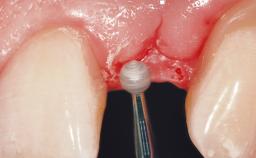

A 30-year-old female patient was referred to the office for the treatment of tooth 11. Her chief concern at the initial visit was to inquire, “Why is my tooth pink?” Upon clinical examination, it was determined that tooth 11 had a previous history of trauma and that the clinical crown had become noticeably pink in color as a result of internal resorption. This diagnosis was confirmed radiographically, indicating a large radiolucency involving the central and distal portions of the clinical crown. It was determined that restoration of this tooth was not possible, and that extraction was indicated. The presence of a mid-line diastema, which the patient wanted to reproduce, directed the treatment plan for tooth replacement utilizing a dental implant.

Placement Protocol Immediate implant placement

Tooth Site Maxillary incisor or canine

Socket Morphology Single-root socket

Socket Integrity Sufficient, with intact bone walls